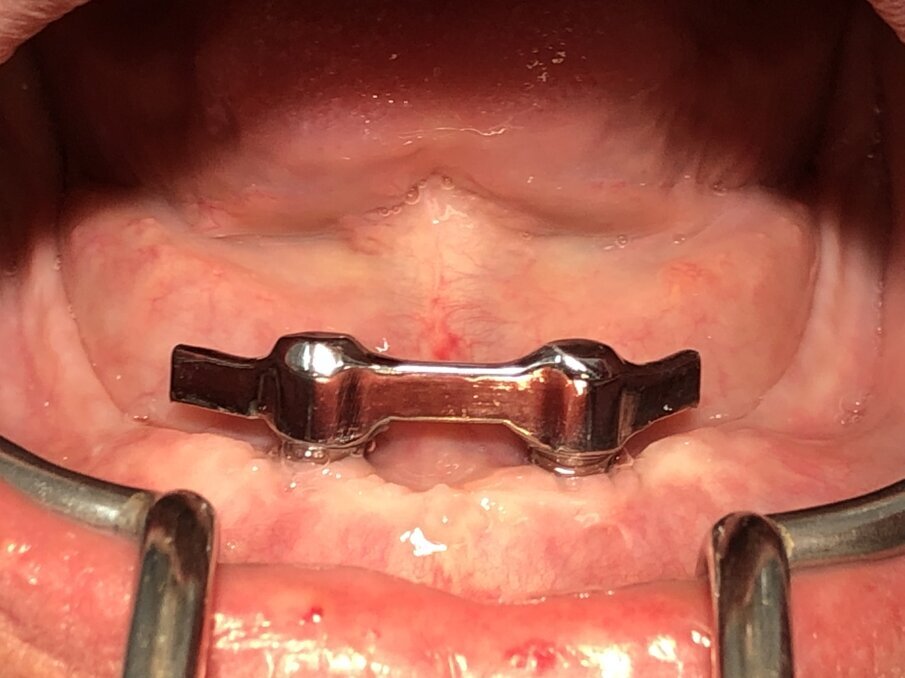

De foto’s van de dolderstaaf in deze publicatie zijn afkomstig van een patiënt, waarvan wij de constructie hebben vernieuwd wegens onvoldoende houvast. Om de dolderstaafconstructie eenvoudiger en sneller in de productie te vervaardigen, wordt vaak een nauwkeurig secundair onderdeel in de prothese achterwege gelaten. Dit betekent dat de huidige prothese zonder precisiebasis wordt geslepen en de dolderstaaf in de prothese wordt gepolymeriseerd zonder een geschikt secundair onderdeel (afbeelding 1, 2, 3, 4 en 5).